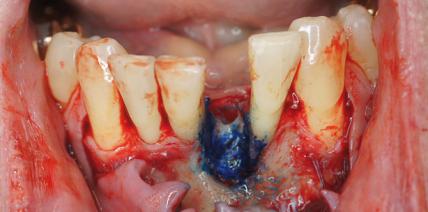

Kollagenmatrix als Ersatz für das autologe Bindegewebs-transplantat

Jahr 2012, Ausgabe 10 Knochen- und Geweberegeneration, Seite 20 Autoren: Dr. Harald P. Hüskens